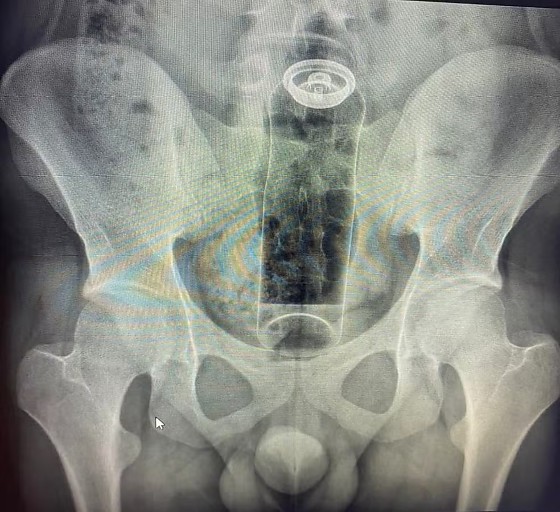

Paciente é internado após ficar com desodorante preso no reto; médicos fazem alerta

De acordo com o médico Daniel Brosco, cirurgião coloproctologista, o paciente tinha 19 anos e contou que colocou o desodorante no ânus durante uma “brincadeira” sexual. A embalagem, porém, acabou subindo para o reto e não conseguiu ser retirada em casa.

“A fantasia não é um problema. O problema é não usar objetos específicos para isso. Imagina se o conteúdo da embalagem vaza ou se o objeto sobe de uma forma que exige cirurgia para retirar? Já tive pacientes que acabaram com infecções graves e morreram”, alertou Daniel Brosco, cirurgião coloproctologista.

O médico conta que os casos têm sido cada vez mais comuns e que, nos últimos meses, já atendeu pacientes em que precisou retirar objetos como batata, partes de uma cadeira, garrafa de vidro e plug anal.